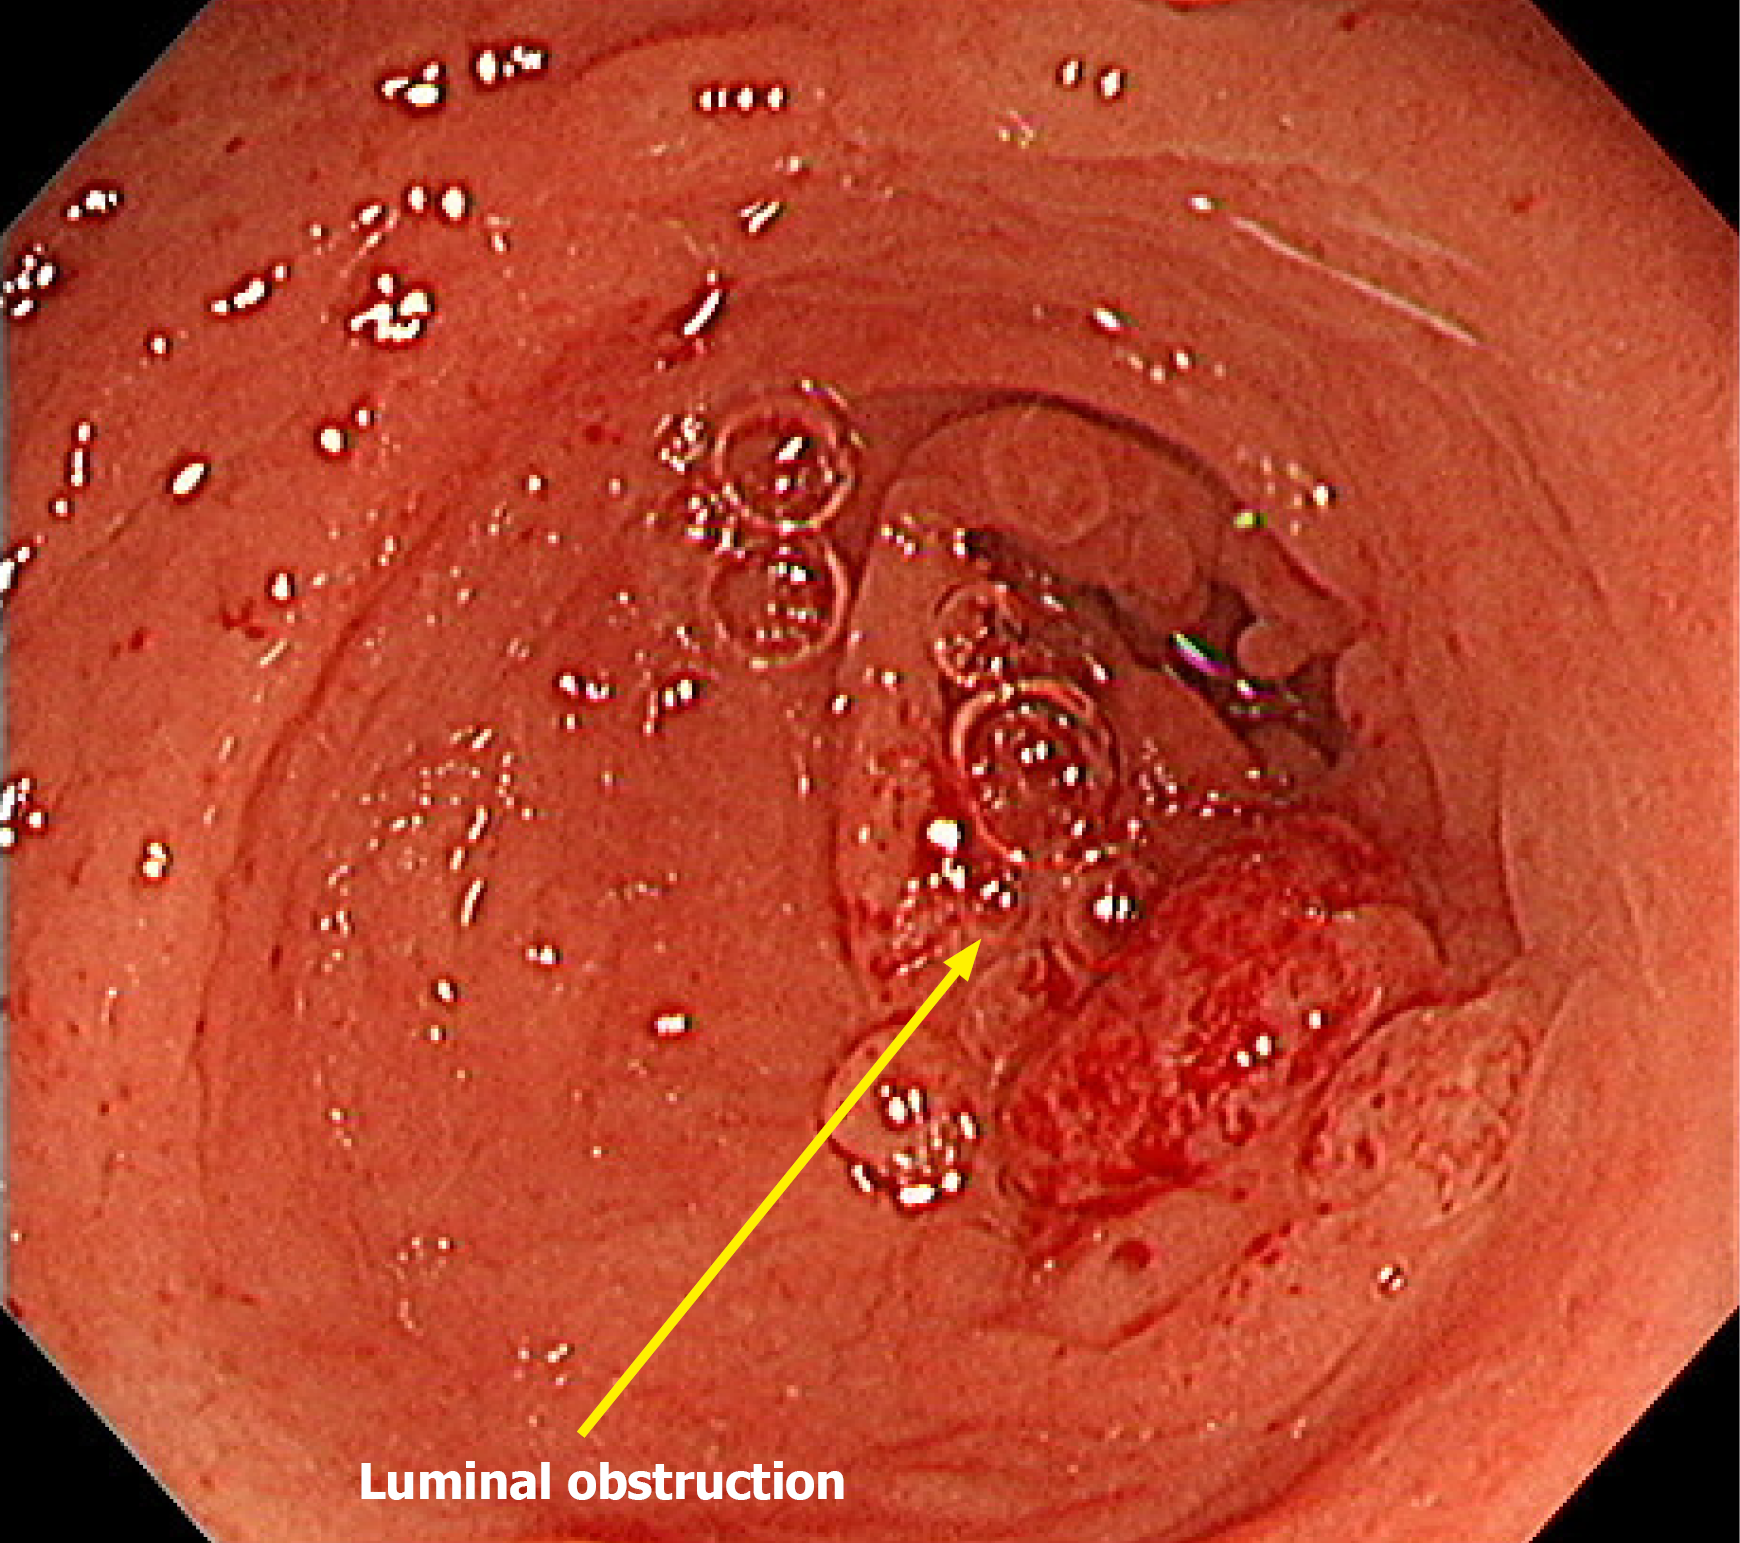

Figure 3 Axial Abdominopelvic computed tomography during the treatment course.

A: Baseline imaging revealed a large soft tissue mass in the proximal transverse colon with invasion into adjacent structures; B: After 6 months of pembrolizumab treatment, a marked reduction in tumor size was revealed; C: After 20 months of pembrolizumab treatment, radiologic complete response of the primary lesion was observed. The yellow circles indicate the location of the primary tumor across the treatment timeline. The orange arrow indicates the primary tumor in the colon with suspected invasion into the pancreas.